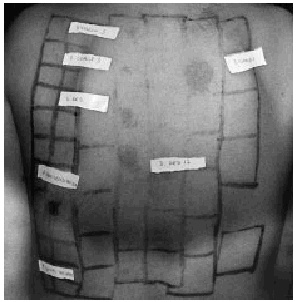

FIG. 3.--Caso 1. Pruebas de contacto a las 96 horas: Reacción intensamente positiva a PPD y muy positiva a los colorantes dispersos yellow 3, red 1, red 17 y orange 1.